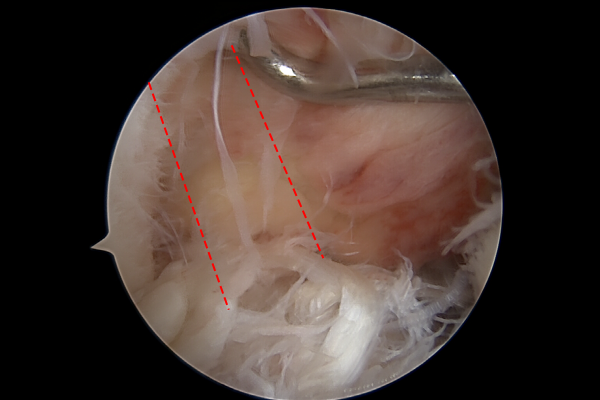

전방십자인대 방향으로 가이드 핀을 삽입하여 십자인대 재건을 할 길을 계획하고서, 구멍을 뚫어줍니다.

이후 가이드 핀 길을 따라서 타가건을 이용하여 전방십자인대를 재건해줍니다.